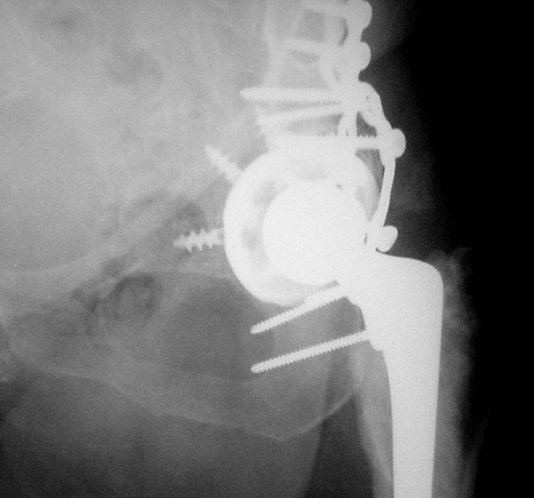

Ножка Алтимед, а чашка цементая???? Хороший гибрид. Насколько позволяет рентгенограмма, можно судить, что чашка стабильна (за счет цемента и арматуры в виде винтов). Нужен постельный режим не менее 6 недель.

Ситуация редкая и нестандартная. Складывается впечатление, что эндопротез вертлужной впадины стабилен. Я бы выполнил остеосинтез перелома в/впадины реконструктивной пластиной. Эти переломы срастаются хорошо.

Если при этом все же вертлужный компонент будет нестабильным, то постарался бы его укрепить винтами и путем компрессии при остеосинтезе (возможно понадобится костная пластика костной крошкой).

Больная оперирована мной по поводу диспластического коксартроза 5-6 месяцев назад.

Установлена RM-чашка бесцементная,ножка тип Цвайммюллер производства Мathys,сделана костная пластика.В настоящее время необходим остеосинтез реконструктивной пластиной без удаления чашки,так как чашка стабильна.